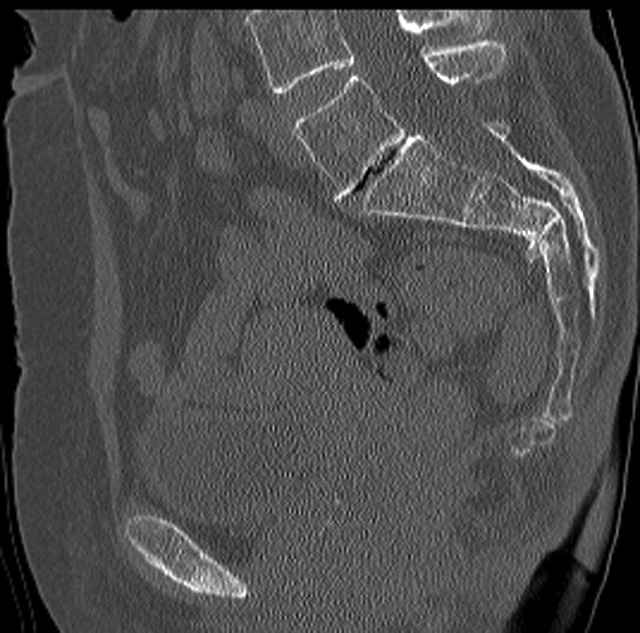

Here are a recent patient’s example slides...

3 Months After Fall

Continued Pain & Immobility

(+) Instability to Compressive Manual Exam

Pelvic CT Scan - 3 Months After Fall

Sacral Injuries

Ramus Fractures

Percutaneous Fixation

(B) Ramus-Retrograde

2 TransIliac-TransSacral

Upper Segment